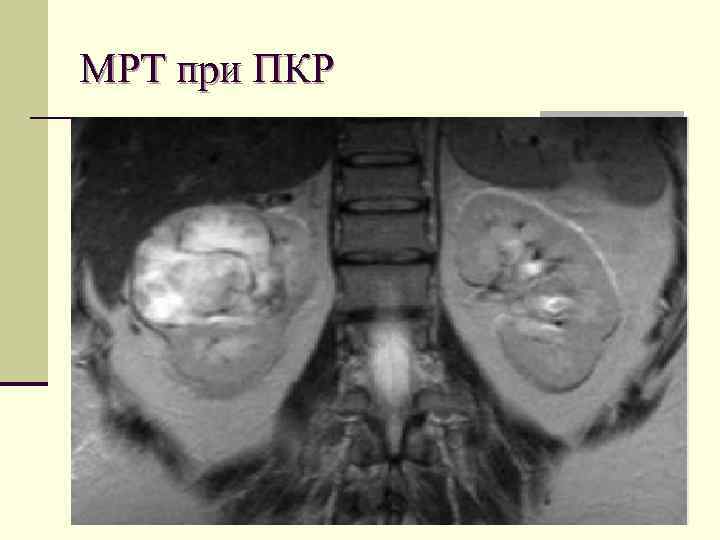

МРТ, как дополнительный метод относительно: n выявления контрастирования в новообразованиях почек n исследования местно развившегося злокачественного образования n неубедительные сведения о степени поражения венозной системы при КТ Hricak H, Demas BE, Williams RD et al. Magnetic resonance imaging in the diagnosis and staging of renal and perirenal neoplasms. Radiology 1985; 154(3): 709– 15.

МРТ при ПКР